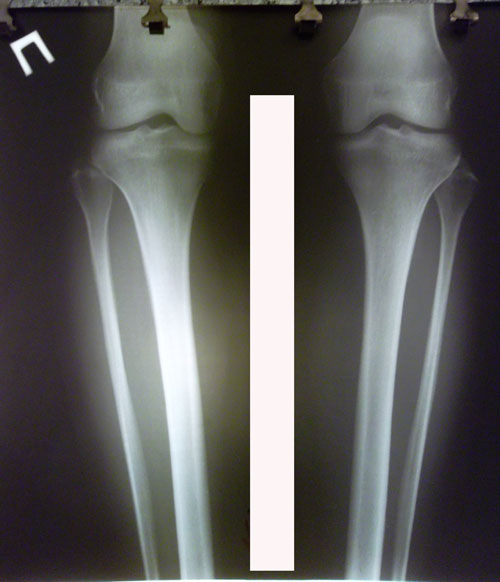

РЕНТГЕН ДО ОПЕРАЦИИ